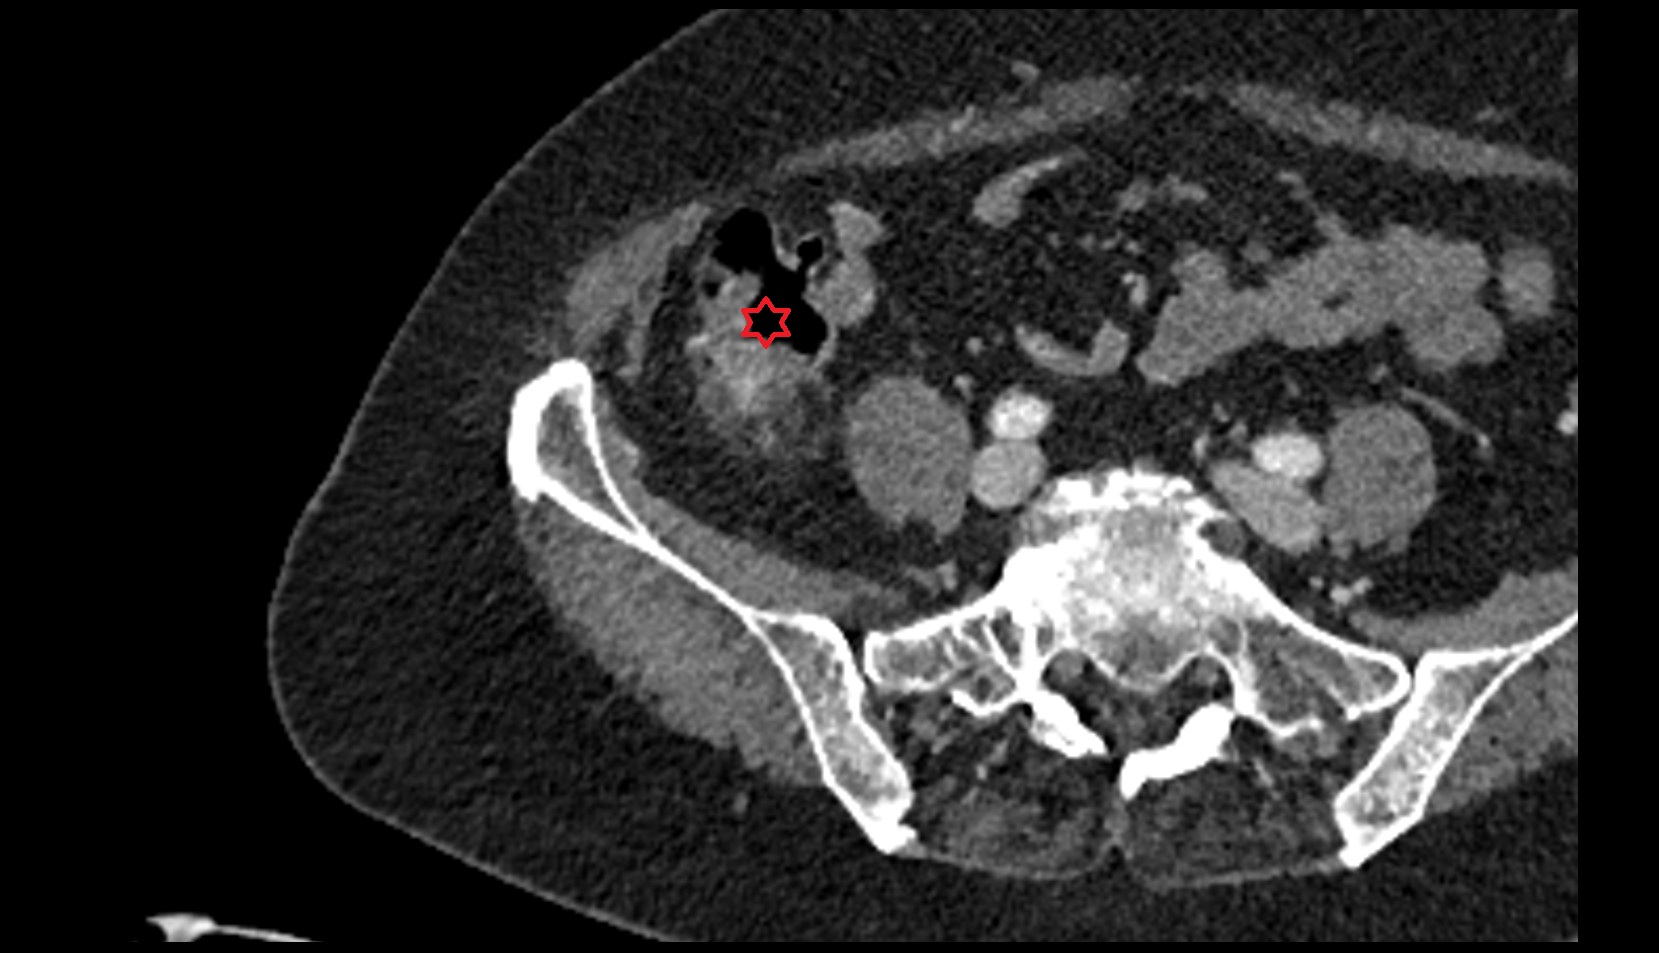

- Rectum

- Mesorectal fascia

- Mesorectum

- Mesorectal free fluid